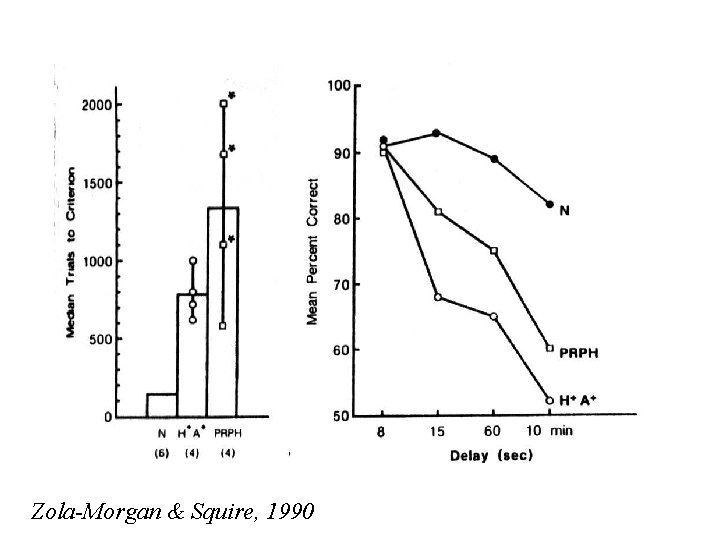

Zola-Morgan & Squire, 1990

Zola-Morgan & Squire, 1990